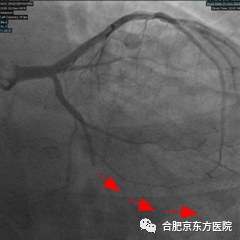

随后的冠脉造影检查证实了医生的判断——耿先生心脏里一根重要血管已经严重堵塞,必须马上手术打通血管。时间就是心肌,心内科胸痛急救医疗团队立即到岗,在孙洪伟主任带领下通过 DSA 介入治疗开通堵塞的心血管。术中 应用药物球囊替代支架植入,通过「介入无植入」的技术手段开通闭塞血管,解除心梗危机。